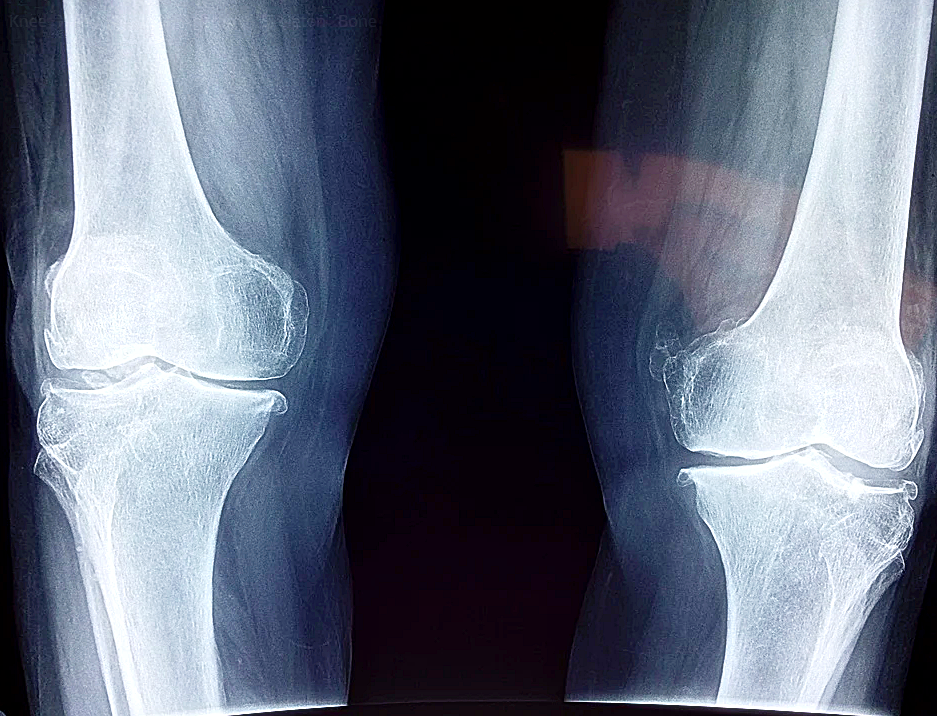

2. 관절 건강

실제로 병원의 퇴행성관절염 치료 주사에서도 많이 사용하는 것이 이 히알루론산 성분입니다. 히알루론산은 연골의 윤활유 역할을 하여서 관절이 부드럽게 움직일 수 있도록 도와주는 역할을 합니다.